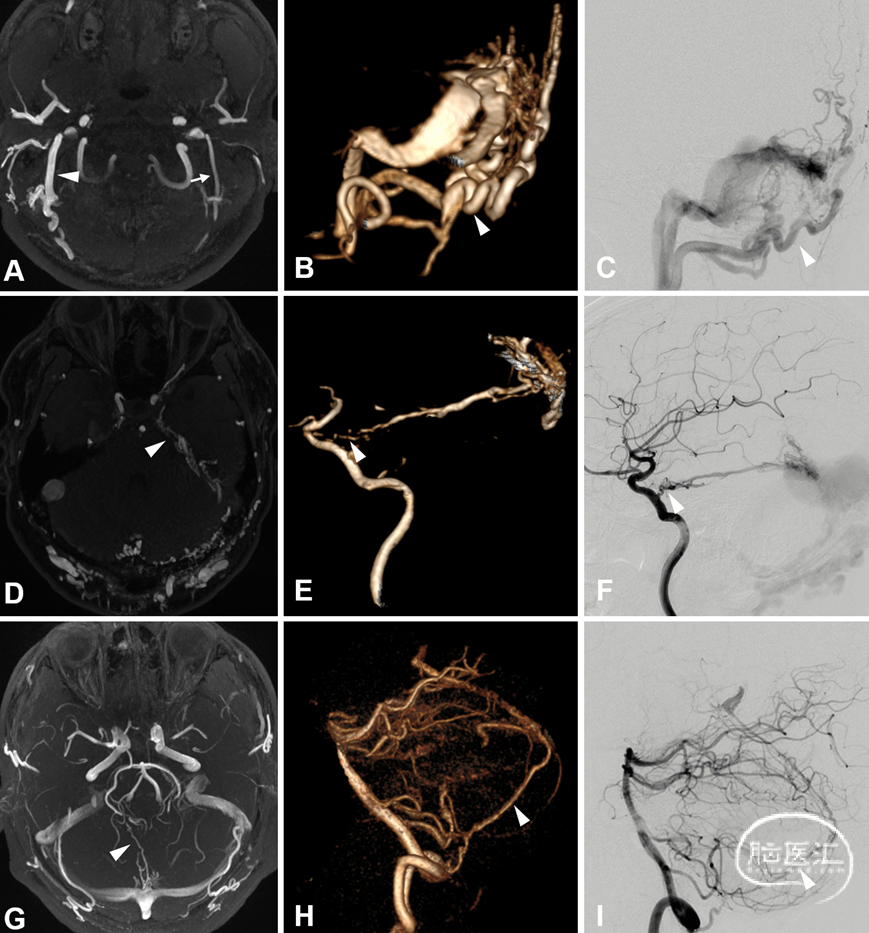

3.2.3 高分辨率磁共振血管壁成像 (MR Vessel wall imaging, MR-VWI)

MR-VWI在DAVF的应用发现自发性破裂的血管壁表现出明显强化的特点。血管壁强化与出血具有一定的相关性,有关强化机制可能是动脉血冲击引起的静脉壁炎性改变,导致局部管壁脆弱而促使血管容易破裂出血。MR-VWI亦可以显示静脉窦腔内结构,提示有无静脉窦血栓,亦可以评估经静脉EVT手术路径的可行性,进而辅助制定手术策略。

图12. 高分辨率管壁成像及DSA图像对DAVF静脉窦腔内结构特征评估。左侧侧窦窦内可见静脉脊结构 (A细箭) 。3D融合DSA (颈内动脉静脉期旋转造影+颈外动脉旋转造影) 证实了静脉脊的存在,静脉脊 (B、C细箭) 将乙状窦分成了两部分,上部负责正常的引流功能,下部为DAVF引流出口。左侧侧窦见静脉脊 (D细箭) 及血栓 (D空箭) 。DSA证实了静脉脊 (E、F细箭) 及血栓 (E、F空箭) 存在。静脉窦内血栓形成静脉脊形态无法分辨 (G空箭) 。DSA证实血栓 (H、I空箭) 存在

图13. DAVF逆流皮层静脉及瘀滞静脉的高分辨率管壁成像及DSA图像。高分辨率管壁成像显示逆流皮层静脉壁 (A、B白箭) 。DSA证实逆流皮层静脉 (E、F白箭) 。高分辨率管壁成像见瘀滞静脉壁 (C、D白粗箭) 。DSA证实此静脉为瘀滞静脉 (G、H白粗箭)